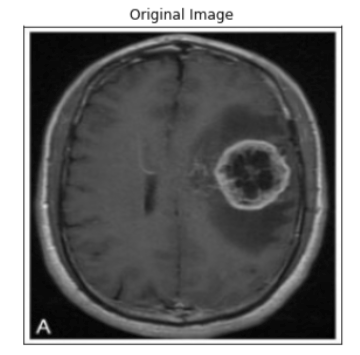

ind = 6

display_image(dataset_val, ind)

predict_and_plot_differences(dataset_val, ind)